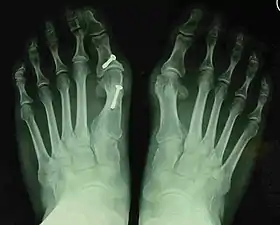

- For recurrence correction after osteotomy procedure (Fig. 8)

Late deformity recurrence can happen after osteotomy (bone-breaking) procedures because osteotomy surgeries do not specifically stabilize first metatarsal bone.

For recurrence correction after fusion procedure (Fig. 9) Metatarsus primus varus deformity and pain recurred 6 months after modified Lapidus procedure and it could also be again corrected by the syndesmosis procedure.